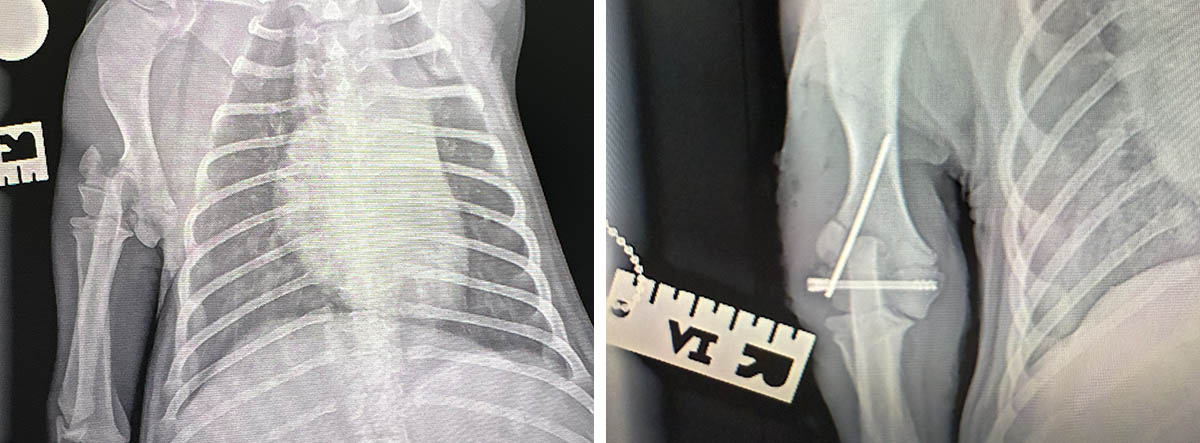

Thankfully, all passengers, human and animal, survived without major injuries. One small puppy, however, sustained a lateral humeral condylar fracture after his crate was crushed in the collision.

Dr. Nicole Mayne from Wildflower Veterinary Surgery promptly offered surgical assistance at the shelter. After radiographic evaluation confirmed the fracture, she performed an open reduction and internal fixation using LEICOM Headless Compression Screws.

The screw’s self-compressive design provided secure interfragmentary compression across the condylar fracture line while minimizing implant prominence, which was ideal for such a small patient. This stable fixation allowed for early functional recovery and reduced postoperative irritation around the elbow joint.

Postoperative radiographs confirmed excellent alignment and stable fixation. The puppy is healing well and is expected to make a full recovery in just a few weeks, ready for adoption and a fresh start with a new family.